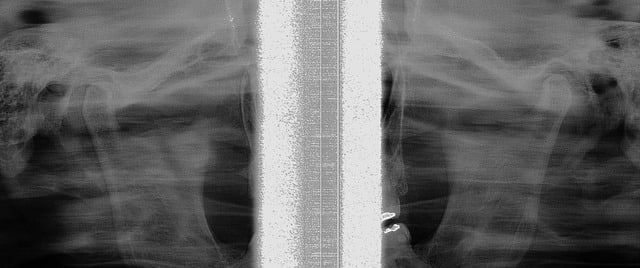

Voici la Tomo actuelle de son condyle G.

Fin de traitement, plus de douleurs coté G. !!!

Confirmé par la dernière tomo des ATM.